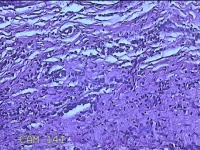

左上后牙根尖肿物

性别

男

年龄

42岁

临床诊断

慢性牙周炎

一般病史

左上后牙残根邀请拔除。

标本名称

大体所见

灰白暗红色肿物1.5x0.8x0.3cm一个,表面光滑,切开肿物呈囊性,囊内有大量脓液,囊壁厚0.2ml,另有牙齿1.5x0.8x0.7cm一颗。